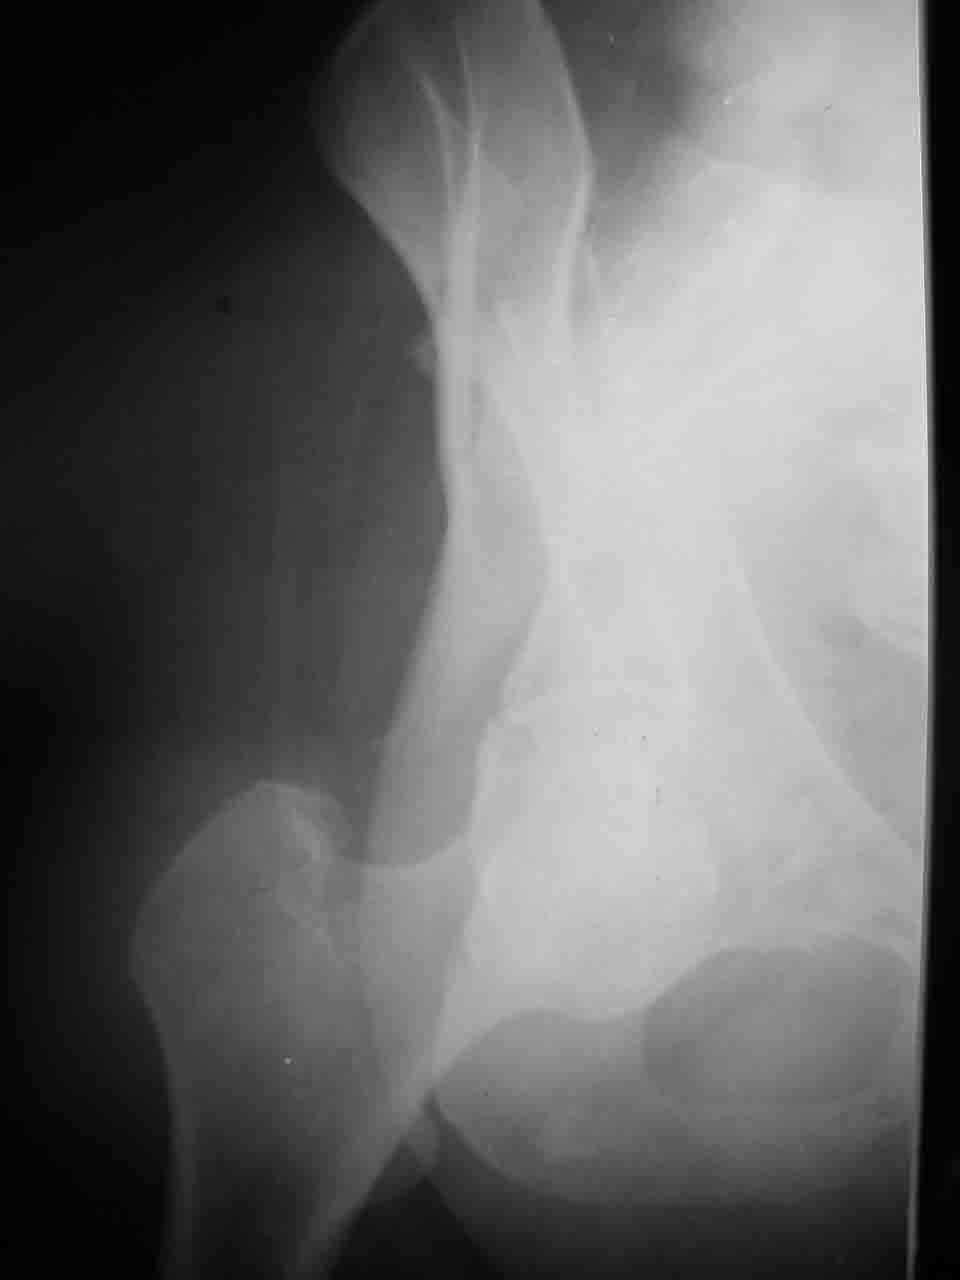

Re: Перелом вертлужной впадины

Причиной обращения к сообществу были возникшие непосредственно после операции сомнения и разочарования полученным качеством репозиции: а надо ли было трогать перелом вообще, репозиция передней колонны технически была очень сложна для меня, хотя реконструкции была в той же последовательности, что Д-р А.В.Рунков рекомендовал, в какой-то момент безуспешных манипуляций стал думать о *вторичной конгруэнтности*, которую не так давно обсуждали на

форуме и скелетном вытяжении. С репозицией и фиксацией задней колонны и отдельно задне-верхней стенки впадины проблем не возникло. Послеоп. Рг граммы в приложении. Если возникнут какие-либо дополнения или поправки - был бы признателен.